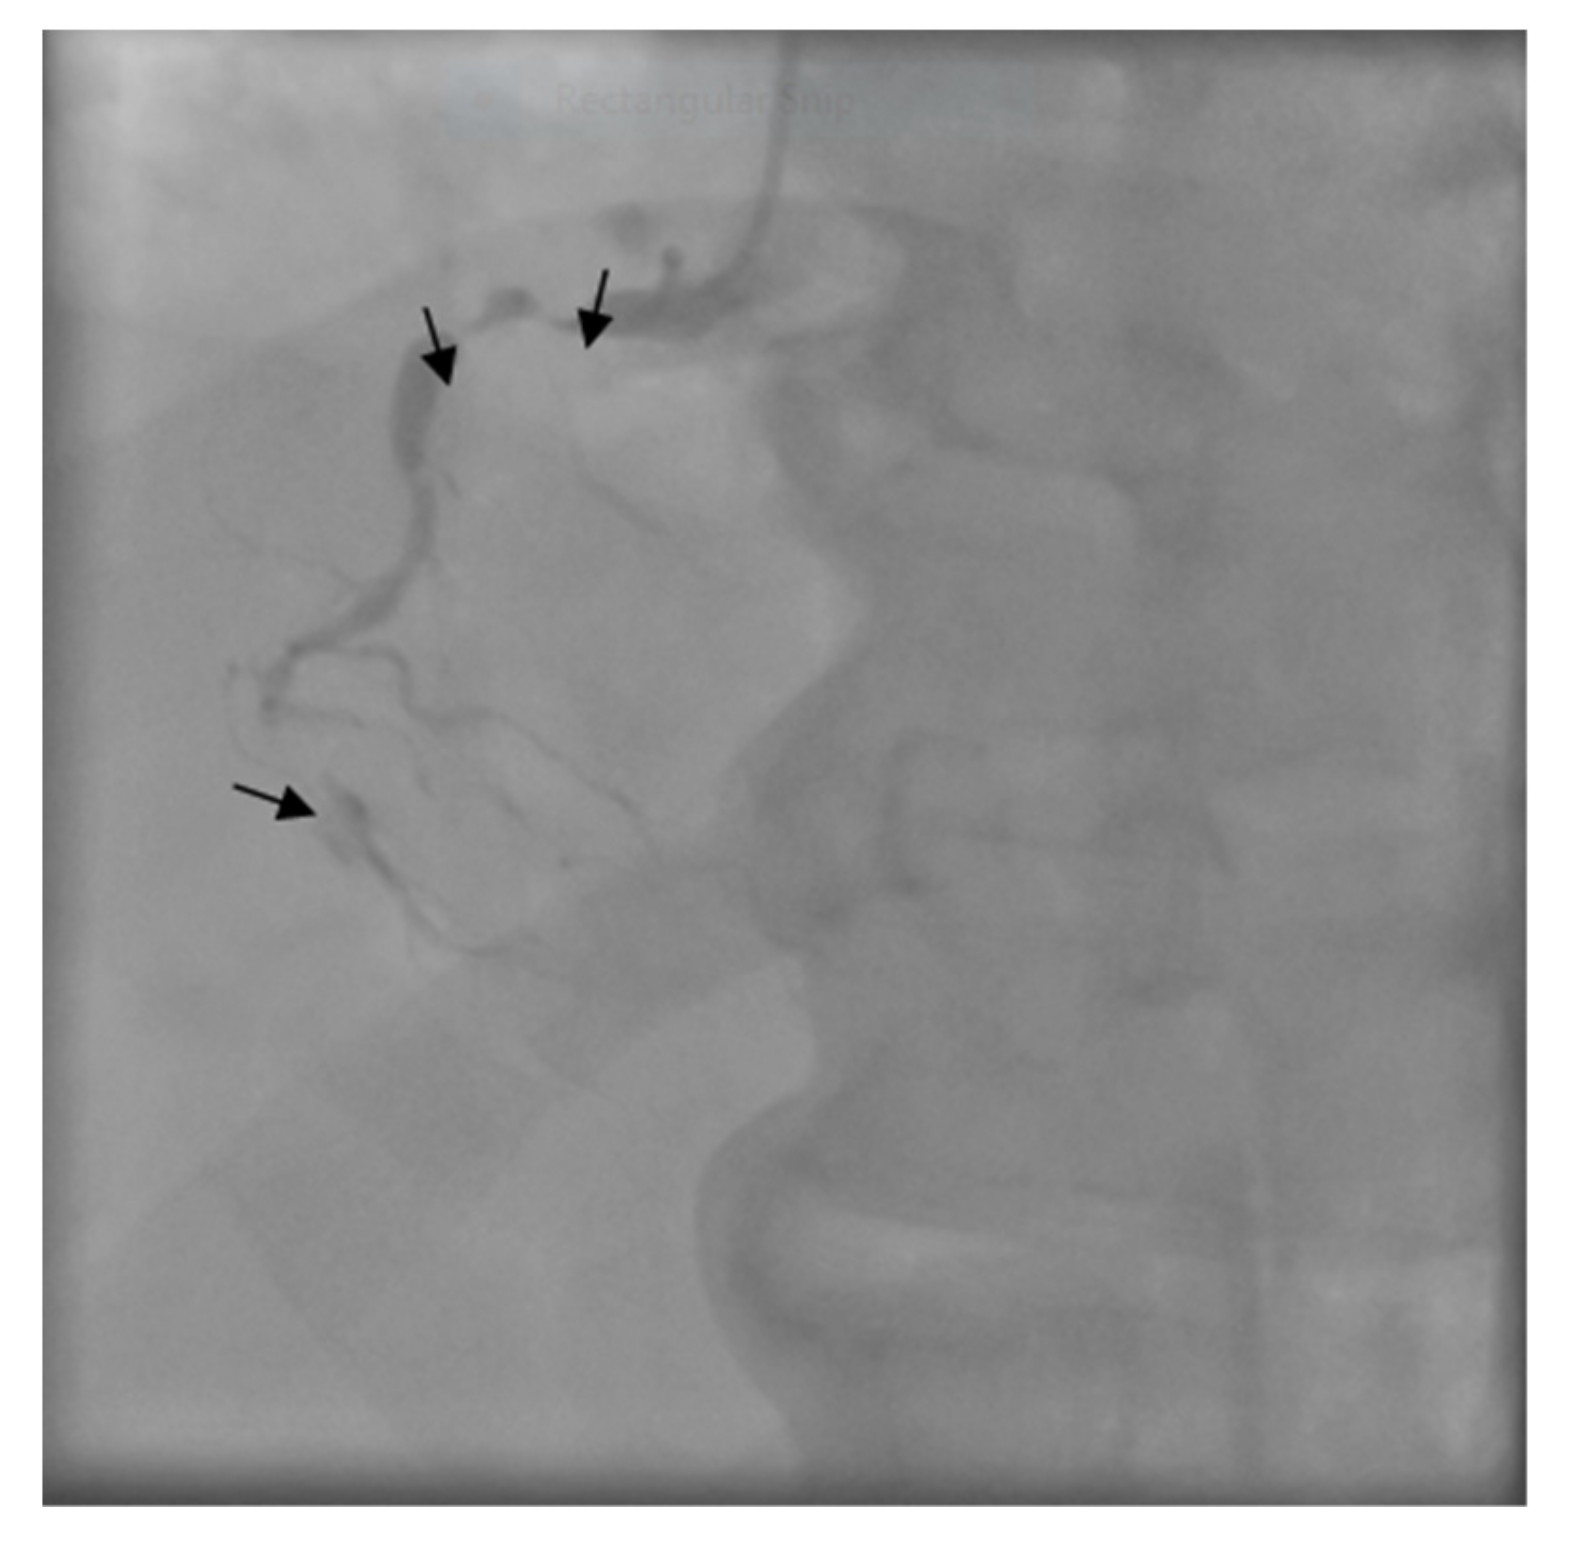

The patient was transferred to the Intensive Care Unit where he received inotropic support with Dobutamine, Levosimendan, and loop diuretics. The coronary angiogram showed a proximal critical stenosis of the left anterior descending artery (LAD) (Figure 5) and a tight lesion of the obtuse marginal (OM1) (Figure 6).

Figure 5. Left coronary angiogram - arrows show severe proximal left anterior descending artery (LAD) stenosis.